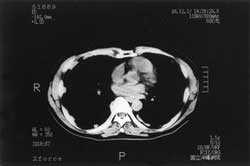

図11.胸膜中皮腫:CT

胸水は肥厚した胸膜により被包化されている